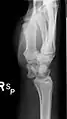

Півмісяцева кістка при вивиху